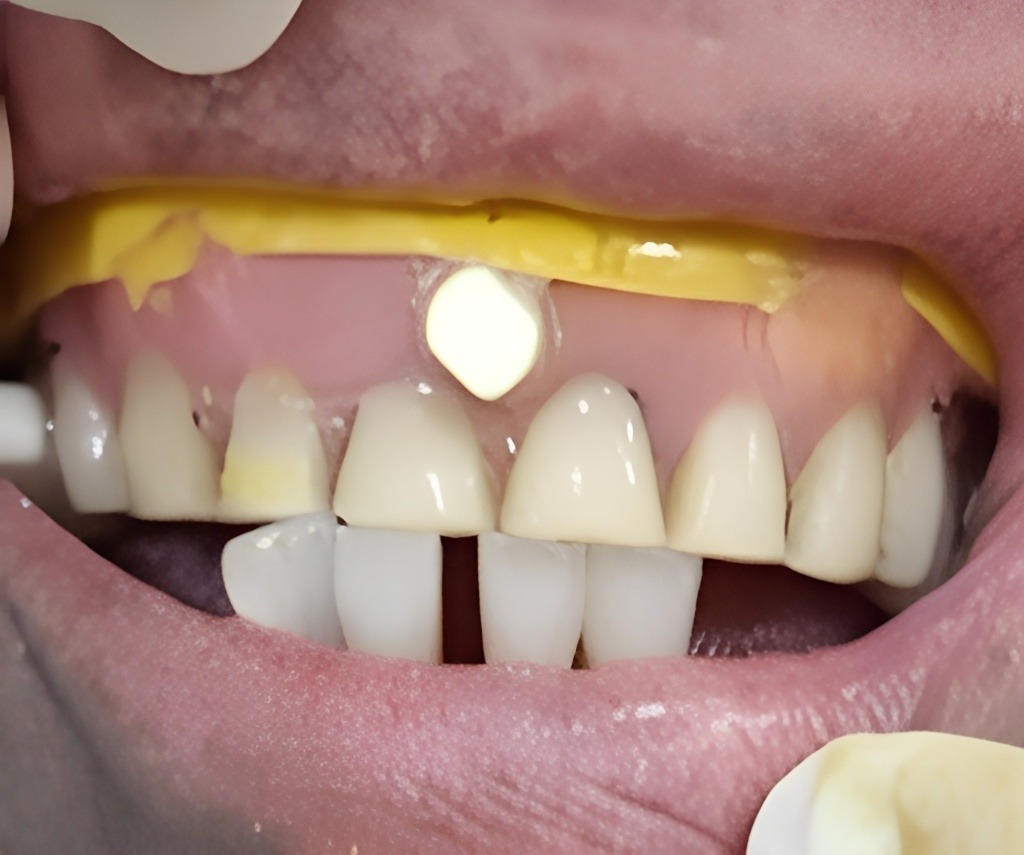

디지털 풀아치 임플란트(상악) & 전체 임플란트(하악) (64세 여성)